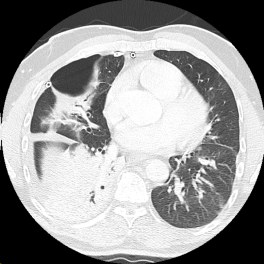

A chest tube was inserted in the emergency department. A CT scan the next day showed a tiny right-sided hydro-pneumothorax and a large cavitary lesion next to the heart.

However, a follow-up CT scan 3 days later showed interval development of a large loculated right pleural effusion, and worsening right middle lobe/right lower lobe opacity.